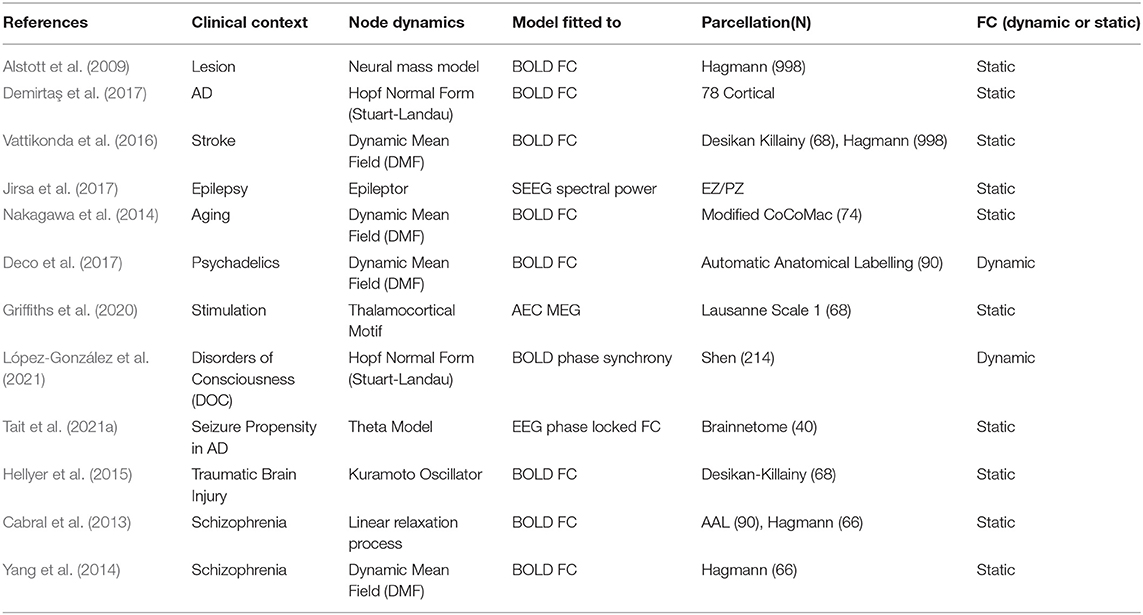

Exemplar BNM studies